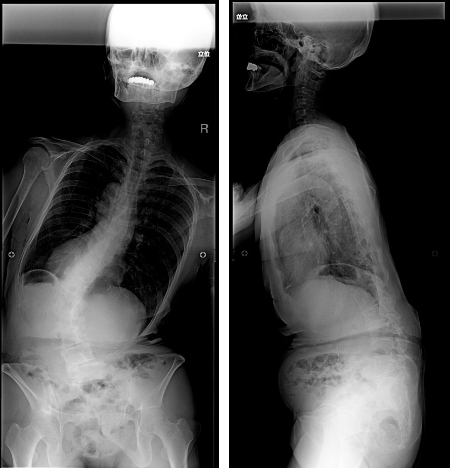

手術前脊椎全長X線写真正面像/側面像